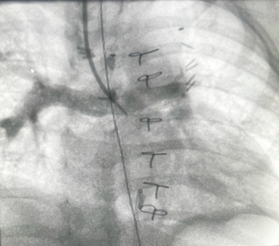

A 13-month-old 8 kg child with hypoplastic left heart syndrome (HLHS) status post Stage 1Norwood followed by bidirectional Glenn at 7 months of age presents for diagnostic cardiac catheterization for hypoxia with oxygen saturation of 60-65%. Superior vena cava (SVC) angiograms demonstrated a diffuse reticular pattern of the pulmonary vasculature, with rapid transit time of contrast into the pulmonary veins, and an absent capillary phase. No decompressing venovenous collaterals were identified on angiography. Indexed pulmonary vascular resistance (PVRi) on FiO2 = 100% and iNO 20ppm was 3.5 WU x m2.

The angiographic findings described -a diffuse reticular pattern, rapid contrast transit time from pulmonary artery to pulmonary veins, and absent capillary phase -are pathognomonic for pulmonary arteriovenous malformations (PAVMs), a known complication following superior cavopulmonary anastomosis (Glenn procedure).